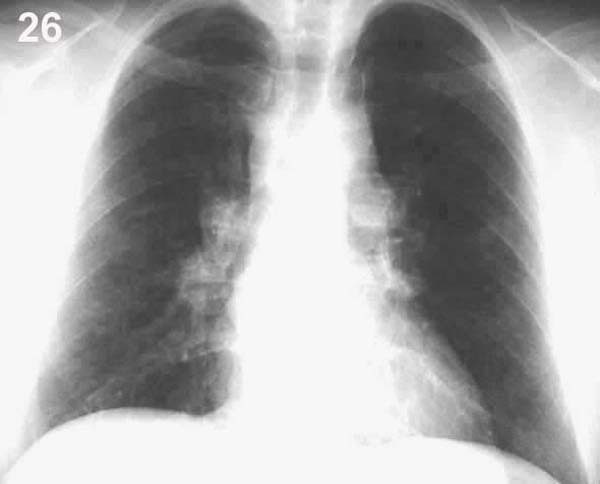

Placa 26